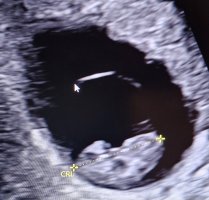

Fikk du høre hjertet når du var så kort på vei? Jeg fikk beskjed at de ikke ønsket å bruke doppler fordi det kunne forstyrre de når de var så små. Fikk bare sett hjertet slå. Jeg var 8+5.Vi hadde privat ultralyd 7+0 (mensdato 7+4), hvor vi hørte hjerteslag, så plommesekken, og lille ble målt til 8 mm og 7+5 (unøyaktig så tidlig sa hun)Vis vedlegget 474796Vis vedlegget 474797